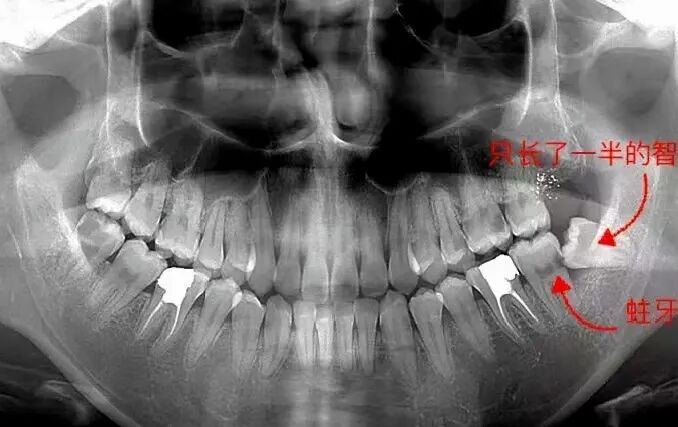

在举个例子,下图这位年轻人的智齿已经生长出来了,但是借助牙片,你会发现,智齿只生长了一段,并且由于方向不对,智齿几乎歪了。

这类型的智齿,是需要拔掉的,可以看到它周边的牙齿由于智齿的生长都快被挤坏了!

曲面断层片怎么看科普知识:你会看牙片嘛?今天手把手教你看!_https://www.jmylbn.com_新闻资讯_第11张